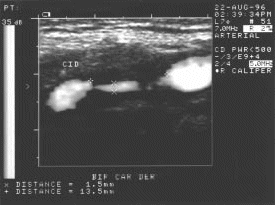

Figura 22.- Vista transversal del caso de la figura 20.